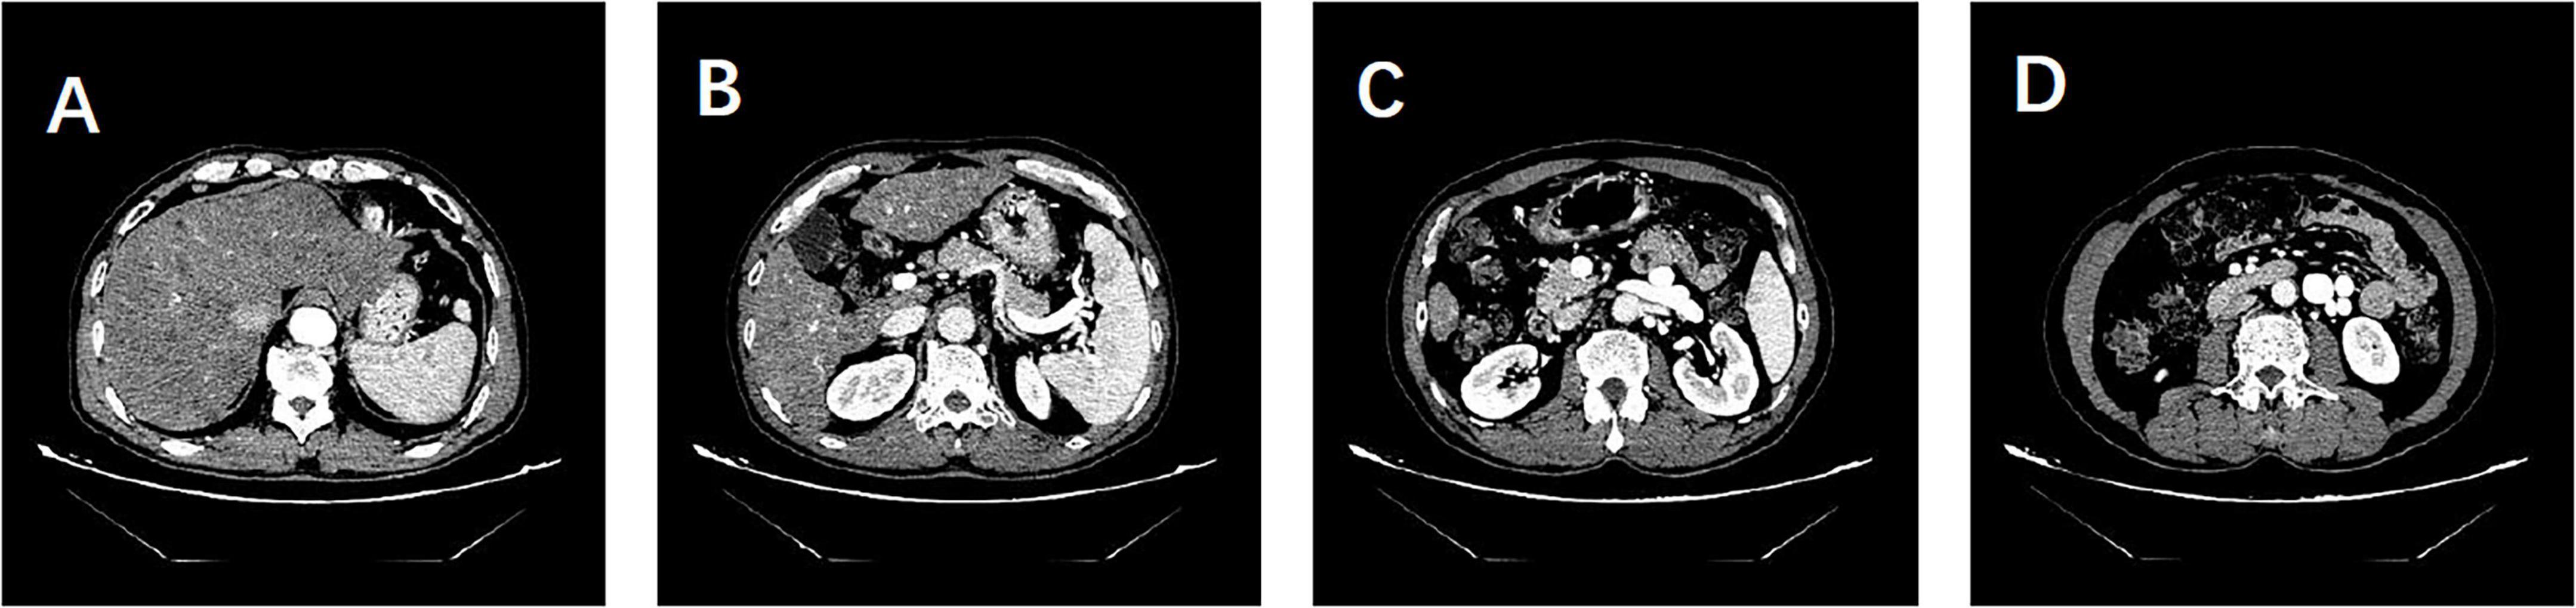

[Abstract] This case report examines the diagnostic and therapeutic complexities presented by a patient with hepatic encephalopathy resulting from overlapping pathologies of non-alcoholic steatohepatitis (NASH), hepatitis B virus (HBV) infection, and non-cirrhotic portal hypertension (NCPH). Highlighting the intricate relationship among these conditions, this study delineates the distinct and overlapping clinical features, diagnostic challenges, and therapeutic approaches. The patient exhibited atypical symptoms typical of NASH but lacked clear signs of cirrhosis, complicating both the diagnostic process and the therapeutic management. The diagnostic journey involved a nuanced assessment using multimodal imaging techniques, which were crucial in distinguishing between hepatic encephalopathy caused by cirrhosis and that due to NCPH. Treatment strategies had to be carefully tailored to address the specific etiological factors and pathology of the conditions involved, with particular attention to managing metabolic disorders such as insulin resistance and abnormalities in lipid and glucose metabolism, frequently observed in both NASH and HBV. The case underscores the need for a comprehensive and individualized approach in managing complex hepatic conditions, especially when conventional diagnostic criteria and treatment protocols face limitations.